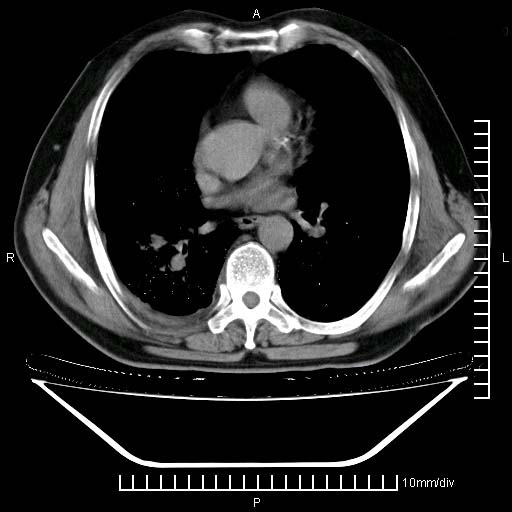

既往肺结核,近10几天,咳嗽,咳痰,右侧胸痛,疼痛较明显,右上肺斑块考虑结核灶胸膜粘连,增强,可惜动脉期没有定好,未见强化,可延迟4分后又见较明显强化,中心见低密度影,如果说结核是边缘强化,可这个灶强化的面积挺大的,让人很挠头。

延迟4分后